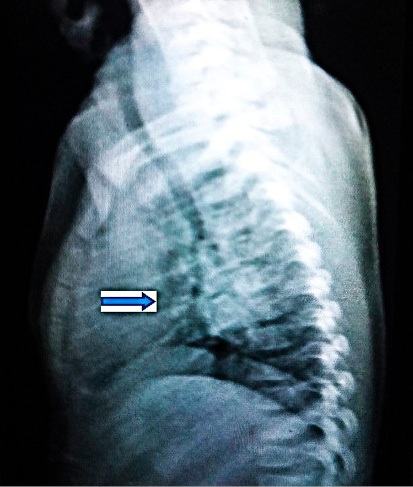

Imagen de radiopacidad, retrocardíaca.

Engrosamiento hiliar derecho e infracarinal (compatible adenopatías de complejo primario tuberculoso).

Paciente femenina de 1 año y medio, no VIH, nacida a término de 38,1 semanas de gestación sin problemas maternos o fetales, con un peso de 3.560 g, talla 51 cm, circunferencia cefálica de 34,5 cm. Parto eutócico, apgar 9/9, sin problemas perinatales y caída del cordón a los 6 días. Lactancia materna exclusiva (6 meses) y complementada hasta el año, con una alimentación balanceada y buena ganancia de peso. Al año de edad, pesaba 10,5 kg. Desarrollo psicomotor y del lenguaje acorde con su edad, camina desde los 12 meses. Niega ingresos, aunque ha tenido 2 episodios de rinofaringitis aguda de corta duración, antes del año de edad; no uso de antibióticos. Asintomática en el momento actual, padre exrecluso que se diagnosticó con TB pulmonar en el año 2024. En las acciones de pesquisa a los contactos, se estudia a la niña que resulta examen físico negativo, asintomática respiratoria, con buen progreso pondoestatural y buen estado nutricional. Peso actual de 12 kg con talla de 78 cm y con un examen físico negativo, sin ningún otro riesgo aparte de la corta edad y ser contacto estrecho de un paciente bacilífero. Vacunación completa para su edad, según normas de nuestro país. La prueba de tuberculina resulta hiperérgica, 18 mm, con presencia de ulceraciones. Se le realiza Rayos x de tórax antero posterior en el cual se sospecha adenopatía hiliar bilateral y subcarinal.

El Centro de Referencia de TB Infantil plantea un diagnóstico de TB pulmonar primaria subclínica y, ante la imposibilidad de obtener muestras respiratorias, se decide enviar la muestra de heces, como recomienda la OMS, al Laboratorio Nacional de Referencia en Tuberculosis del Instituto Pedro Kourí, para realizar el ensayo molecular Xpert® MTB/RIF Ultra; utilizando como método previo para el tratamiento de las heces el Sistema Simple de un Paso (SOS, KNCV TB Foundation, Hague, Netherlands).8 Se les explica a los padres en qué consiste el estudio, beneficios del mismo y se les pide su consentimiento para realizar la prueba, dando como resultado: MTB Detectado Trazas/ Resistencia a la Rifampicina Indeterminada. Se decide iniciar el tratamiento de primera línea para TB sensible a fármacos, según programa, con las cuatro drogas (isoniacida, rifampicina, pirazinamida y etambutol) en la primera fase (60 dosis, según peso de la paciente) y una segunda fase diaria acortada también de 60 dosis, por tratarse de un caso no severo.7 La medicación es bien tolerada, con buena ganancia de peso y resolución radiológica, por lo que termina con éxito el tratamiento. Se mantiene en seguimiento por consulta durante dos años, de acuerdo al protocolo vigente. Por la naturaleza paucibacilar de la TB en estas formas primarias y la rápida resolución radiológica, no se realiza toma de muestra para examen directo y cultivo del contenido gástrico en ayunas por ser un proceder invasivo, no aceptado por los padres. En estos momentos el padre también tiene alta epidemiológica con cultivos negativos.